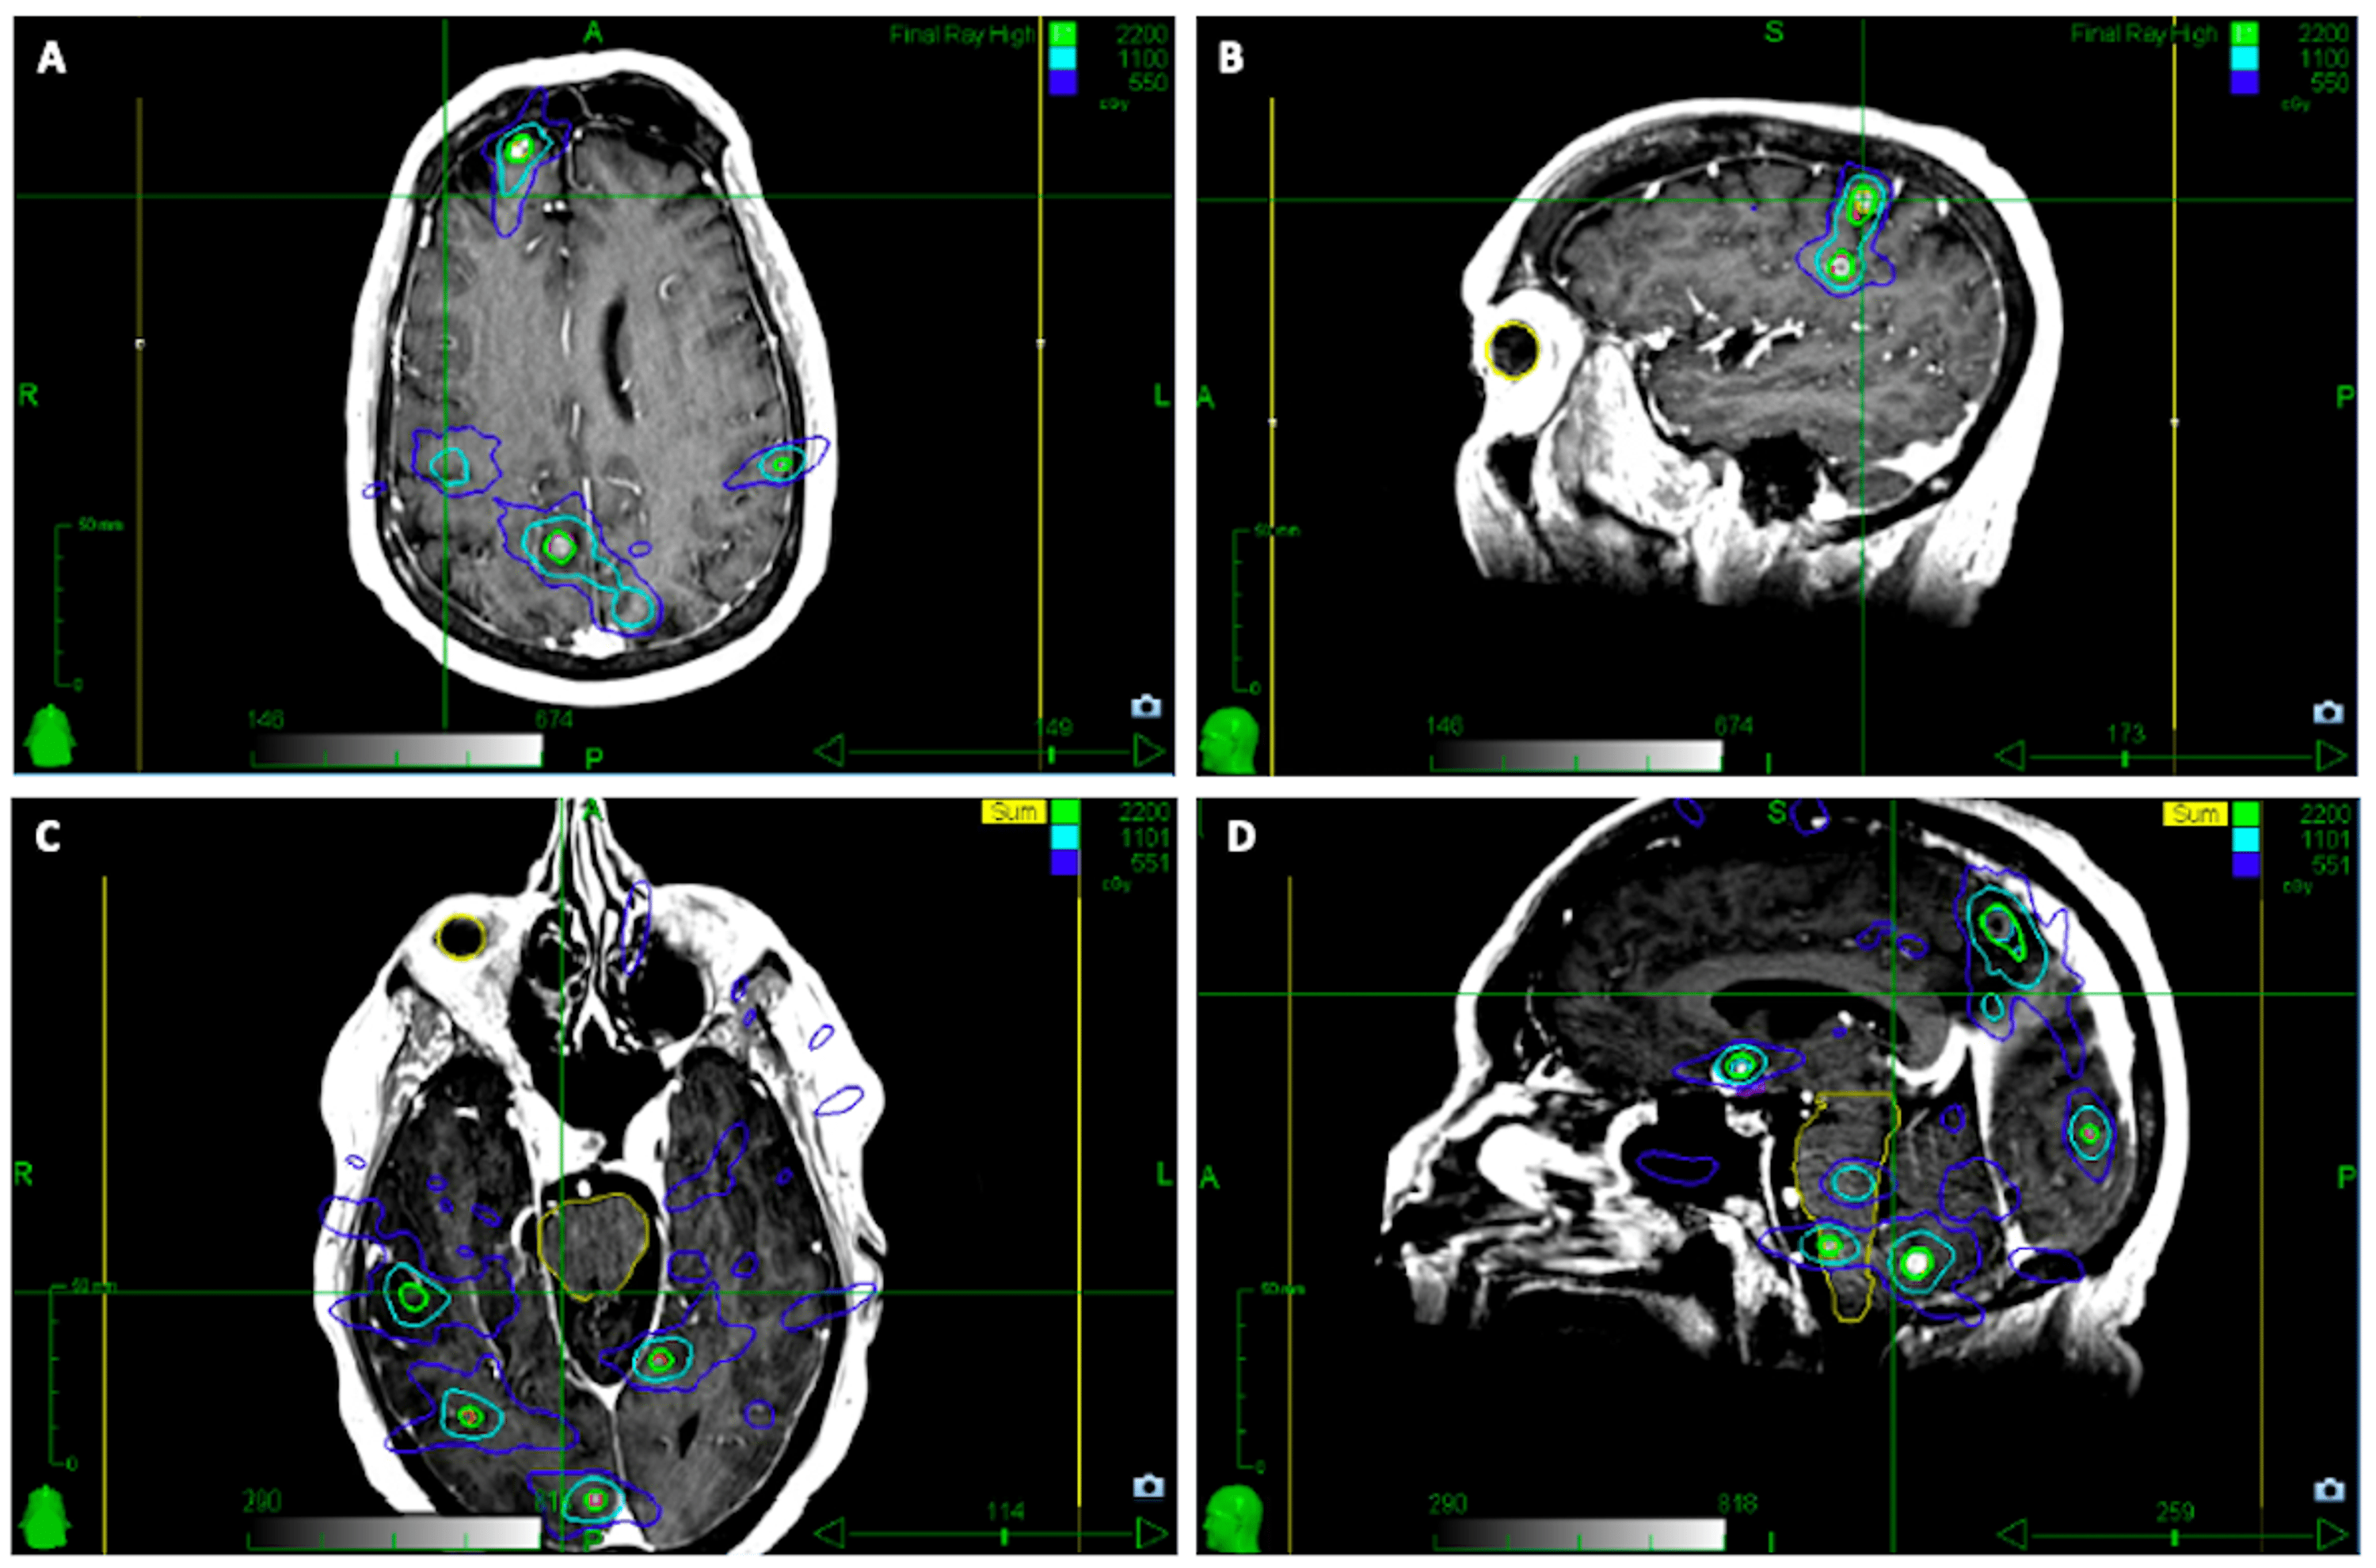

Figure 1, Examples of SRS and SBRT treatment plans for melanoma Stereotactic Radiosurgery To Brain Metastases Brain metastases are the most common intracranial malignancy and remain a substantial source of morbidity and mortality in. While guidelines for srs use have been. Stereotactic radiosurgery (srs) is a mainstay treatment option for brain metastasis (bm). Radiation and steroid dosing can affect the immune composition of brain metastasis (bm). A phase 3 trial of whole brain radiation therapy and. Stereotactic Radiosurgery To Brain Metastases.